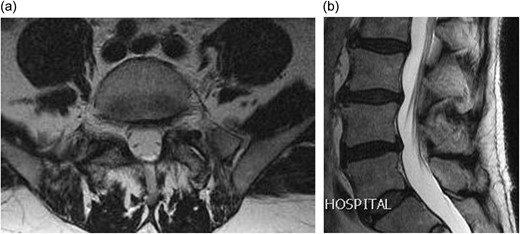

CLINICAL DETAILS

A 66-year-old male presented to our institution with 12 months history of severe back pain and left leg pain in L5/S1 distribution. On examination he had a normal neurology except for a dull left ankle jerk. Magnetic resonance imaging (MRI) of his lumbo-sacral spine showed a left L5/S1 synovial cyst (Fig. 1a and b). The findings and management options were discussed with the patient, who decided for a surgical option. However in view of his recent cardiac history it was decided to see him again in clinic in 6 months’ time. After reviewing him in clinic, he was added to the surgical waiting list and as his MRI scan was a year old, fresh set of scans was requested nearer to his operation date. Surprisingly his repeat MRI showed complete resolution of the L5/S1 synovial cyst (Fig. 2a and b).

(a) Axial T2 weighted MRI showing a left sided L5/S1 synovial cyst impinging on the left S1 nerve root; (b) sagittal T2 weighted MRI showing a L5/S1 synovial cyst.